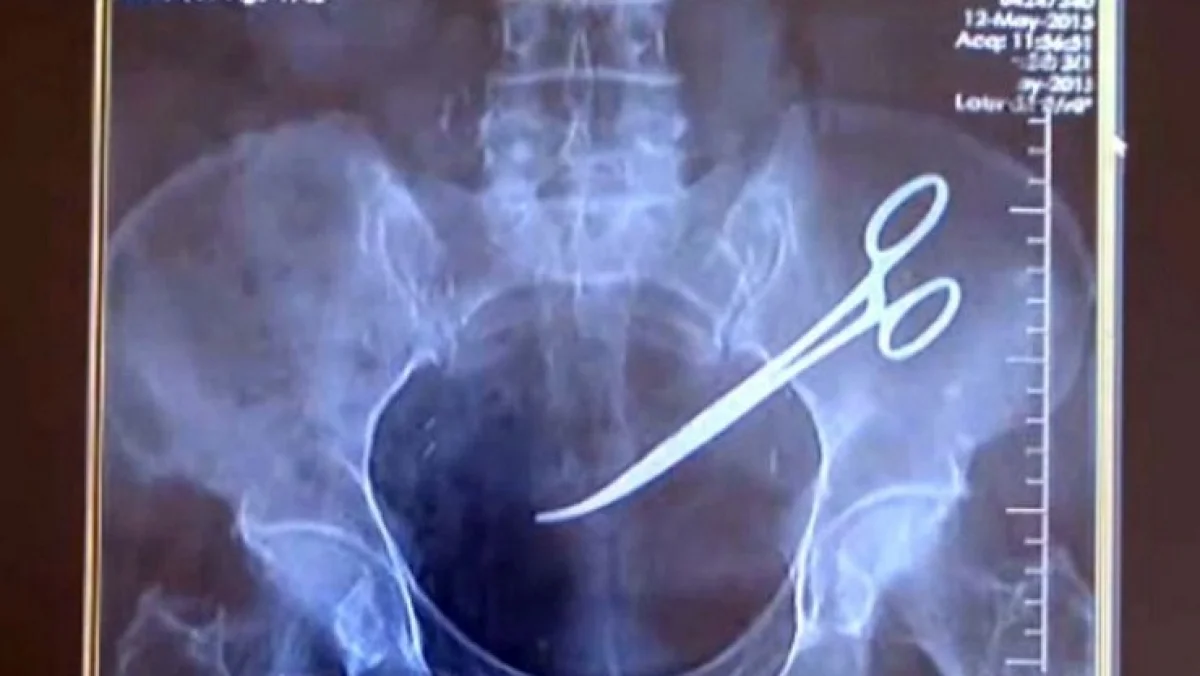

பிரசவம் முடிந்தது வயிற்றில் கத்தரிக்கோல் வைத்து தைத்த டாக்டர்: இழப்பீடு வழங்க நீதிமன்றம் உத்தரவு

அறுவைசிகிச்சை பிரசவம் முடிந்த பின் கத்தரிக்கோலை வயிற்றிற்குள் வைத்து தைத்த டாக்டர் ஒருவர் மீது வழக்கு தொடர்ந்த நிலையில் அந்தப் பெண்ணுக்கு நஷ்ட ஈடு வழங்க நீதிமன்றம் உத்தரவிட்டு இருப்பது பெரும் பரபரப்பை ஏற்படுத்தி உள்ளது

கடந்த 12 ஆண்டுகளுக்கு முன்னர் சென்னை ராஜீவ்காந்தி அரசு மருத்துவமனையில் ஒரு பெண்ணுக்கு அறுவை சிகிச்சை மூலம் குழந்தை பிறந்தது.  குழந்தை பிறந்தவுடன் தையல் போடும் போது கத்திரிக்கோலை வயிற்றுக்குள்ளேயே வைத்து தைத்ததாக தெரிகிறது

இதனை அடுத்து இது குறித்து பாதிக்கப்பட்ட பெண் நீதிமன்றத்தில் வழக்கு தொடுத்த நிலையில் 12 ஆண்டுகளாக நடந்த இந்த வழக்கு தற்போது முடிவுக்கு வந்துள்ளது. இந்த வழக்கில் ரூபாய் 10 லட்சம் இழப்பீடு வழங்க தமிழக அரசுக்கு மாநில மனித உரிமைகள் ஆணையம் உத்தரவு பிறப்பித்துள்ளது. இதனால் பெரும் பரபரப்பு ஏற்பட்டுள்ளது